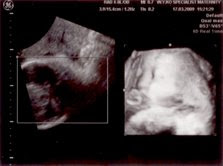

Nie pulak gambar scan mase 33 minggu nak masuk 34 minggu...mase ni ikut hubby outstation ke kuantan. Sebelum ni saye memang bekerja di kuantan, so dapat info dari kwn ade satu klinik yang boleh scan 4D dengan harge paling murah...cume RM70 je. Kalau klinik lain maybe dalam RM150++ kot..X survey laks kat klinik lain brape hargenye. Kwn2 yang byk bg informasi sbnrnye... So, alang2 dah balik smule ke kuantan pegilah klinik ni utk scan. Hubby yang beria2 , kalau ikutkan saye malas sbnrnye..He3!!

Yang kat atas tu gambar baby, nampak muke die dgn mate, pipi , hidung dan mulut sikit je dari tepi. Yang kat mulut die tu bukan puting susu yea...tapi tali pusat. Mase ni kedudukan baby mengiring ( still malu2 la tu kot ) so x dapat nak tgk keseluruhan muke dan badan die. X sabar rasenye nak tunggu baby keluar. he2!!